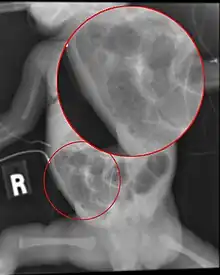

Radiograph of a baby with necrotizing enterocolitis

Diagnosis is usually suspected clinically, but often requires the aid of diagnostic imaging, most commonly radiography, which can show the intestines and may show areas with death tissue or a bowel perforation.[18] Specific radiographic signs of NEC are associated with specific Bell's stages of the disease:[19]